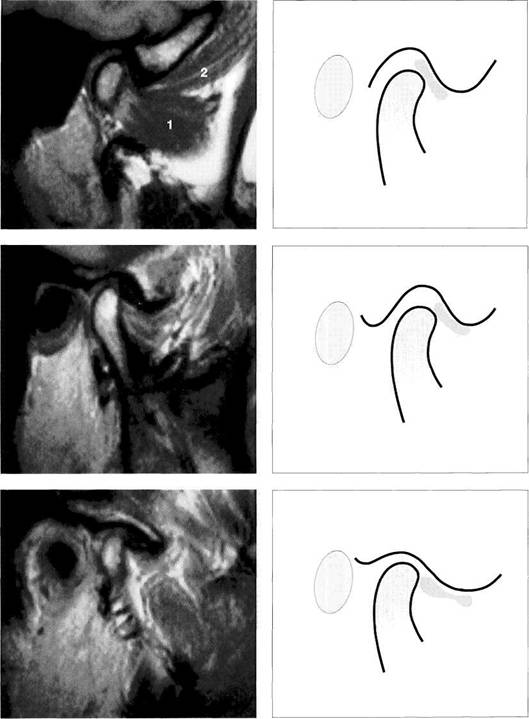

Physiological disk position

Under normal conditions, the pars intermedia (*) of the disk lies be­tween the anterosuperior curva­ture of the condyle and the articular protuberance (arrows). The posi­tion of the posterior border of the pars posterior relative to the vertex of the condyle varies according to the inclination of the protuberance and is therefore not a reliable pa­rameter.

The arrows in this schematic draw­ing mark the relative positions of the condyle and the pars interme­dia to one another.

Insidious disk displacement or a tendency to anterior disk displacement

The pars intermedia lies well in front of the shortest distance be­tween condyle and protuberance (arrows), but the pars posterior (1) still lies on the condyle. Clinically, there are no clicking sounds during jaw opening.

Right: Drawing of a joint with a ten­dency to anterior disk displace­ment. The arrows mark the discrep­ancy between pars intermedia and condyle.

Definite disk displacement

Left: Both the pars intermedia (*) and the posterior border of the pars posterior lie in front of the most anterosuperior curvature of the condyle (arrows). Unless this is a case of disk displacement without repositioning, a clicking sound will occur regularly during jaw opening.

Right: Schematic drawing of a defi­nite anterior disk displacement. The arrows mark the discrepancy between the pars intermedia and condyle.